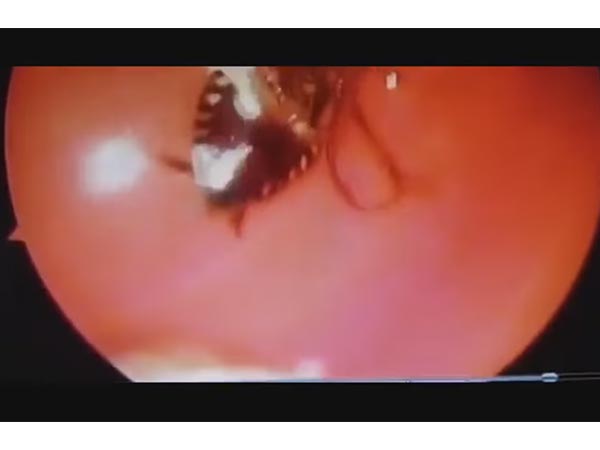

WTF! Cockroach Found In A Woman's Nose!

The favourite pastime of insects seems to be squeezing in any given place and this cockroach chose a woman's nostril! Find out more...

Scans revealed the creepy crawly was sitting in the skull base between her eyes. The scariest part is, it was still alive and its antennas were moving!

The doctors had a tough time pulling out this little monster that was clinging on to the nerves inside her nostril! Hence, doctors took an entire 45 minutes to just pull him out!

Check out the creepy video where the doctors are having a tough time pulling out the cockroach!